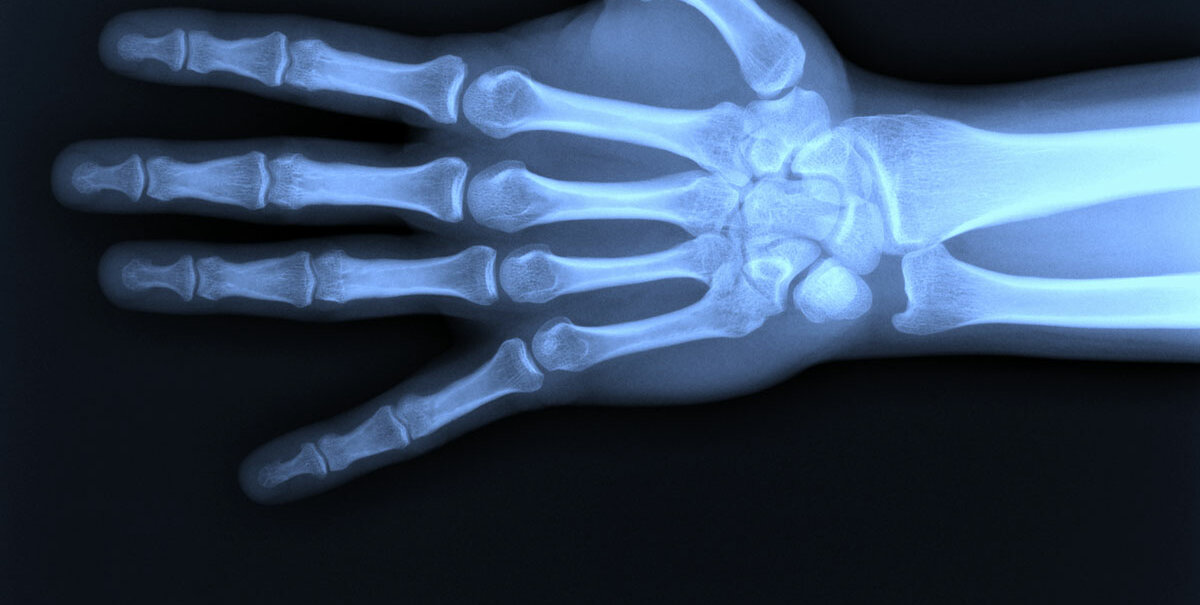

Und letztere beschert ihm auch die „neue Art von Strahlen“. Am 8. November entdeckt er sie. Er schließt sich ins Labor ein, schläft und isst sogar dort, bis er sich sicher ist, dass er sie gefunden hat – eine alles durchdringende Kraft, die in der Lage ist, das Innere des Körpers abzubilden. Zum Beispiel schießt er das berühmt gewordene Foto von der Hand seiner Frau, an der die Knochen der Hand sowie der Ehering klar zu erkennen sind. Das Bild entsteht am 22. Dezember 1895. Fünf Tage später verfasst er eine vorläufige Mitteilung an die Physikalisch-Medizinische Gesellschaft in Würzburg sowie Sonderdrucke an die Kollegen. Bereits am 5. Januar steht ein großer Artikel in der Wiener Presse, der auch auf die Möglichkeiten eines Einsatzes in der medizinischen Diagnostik hinweist – einen Tag später geht die Entdeckung des Würzburger Professors über die Nachrichten in alle Welt.

Das Besondere an der Röntgenstrahlung ist die Tatsache, dass sie Materie durchdringen und abbilden kann – so war es möglich, erstmals Bilder vom Innern des Körpers zu machen. Der Physiker Wilhelm Conrad Röntgen entdeckte sie im Jahr 1895 zufällig. Ohne zu wissen, welcher Natur sie war, nannte er sie X-Strahlung. Röntgenstrahlung hat Wellenlängen zwischen 10 milliardstel Metern (10 Nanometern) und 0,01 Nanometern. Es handelt sich also um elektromagnetische Wellen sehr kurzer Wellenlänge. Die Strahlung entsteht, wenn in einem Atom die inneren Elektronen ihre Bahn um den Kern ändern und dabei Energie abgeben, oder wenn schnelle Elektronen um die Kurve fliegen oder abrupt gebremst werden.